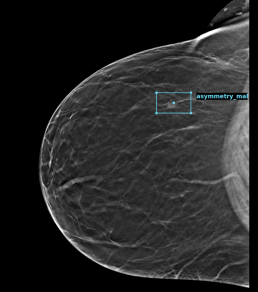

During the mammography reading, the radiologist finds a suspicious asymmetry and possible distortion on the right breast in CC, both on 2D and on tomosynthesis, without finding a match in MLO.